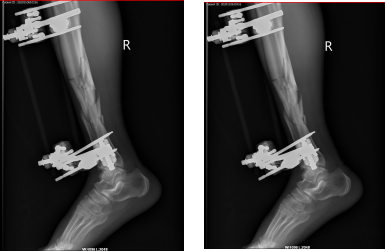

病例分享

67岁的戎先生在家中不慎摔伤,致右胫腓骨开放性粉碎性骨折。

[术前检查]

外固定支架创伤小更有利于术后恢复,对于开放性骨折或感染无法第一时间进行内固定的患者,外固定支架无异于最优选择,外固定支架已广泛应用于治疗骨折、矫治骨与关节畸形和肢体组织延长。